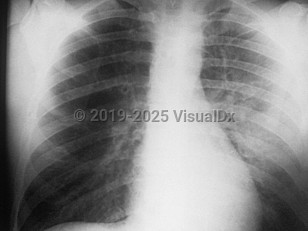

Skin petechiae, Fever, 50-59 year old Female